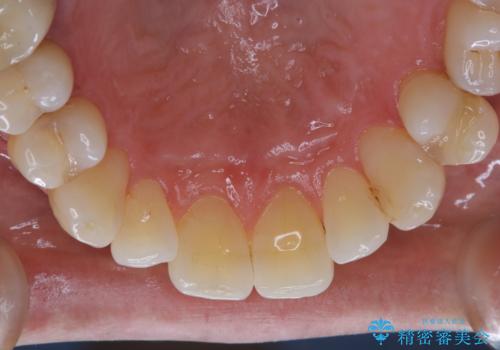

- PMTCでのメンテナンスを定期的に行っている方です。PMTC30分コースを行いました。

日々の磨き残しなどをそのまま放置すると、細菌が固まり硬い歯石になります。

歯石になってしまうと、とても硬く、歯ブラシで取り除くことが出来なくなります。

よって、歯科衛生士による専門的なクリーニングを定期的に行うことがとても大切です。

メンテナンスの間隔は個人差がありますが、基本的には2~3カ月に一度行うことをおすすめしています。